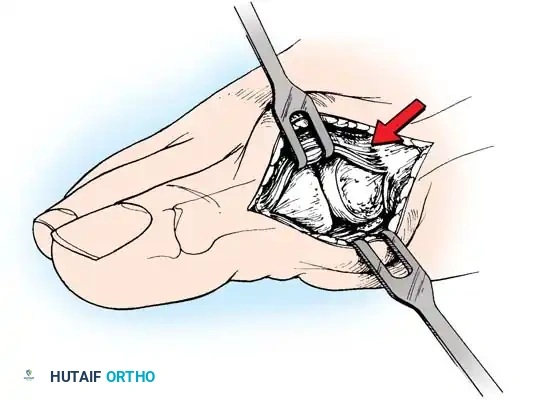

Fig. 78-15 Modifi ed McBride procedure. Capsule is opened, and attachment of capsule on metatarsal neck (arrow) is carefully preserved.

• Grasp the fi bular sesamoid with a small Kocher clamp or sturdy tissue forceps, and pull it laterally into the intermetatarsal space (Fig. 78-20).

• Release the intersesamoid ligament. When this ligament has been incised, bring the fi bular sesamoid into the intermetatarsal space, where its removal is straightforward. Care must be taken when incising the intersesamoid ligament to avoid severing the fl exor hallucis longus tendon immediately plantar to it. If the tendon is severed, it probably should not be repaired at this level; loss of the tendon causes little if any functional impairment, and

Fig. 78-20 Modifi ed McBride procedure. Fibular sesamoid is removed.